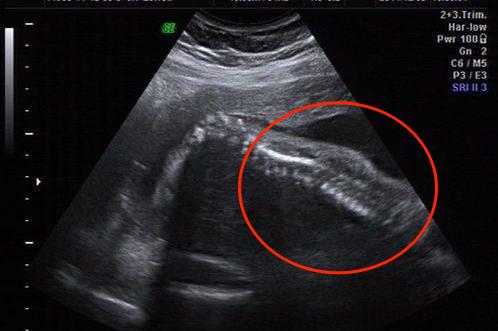

脊柱裂:部分椎管未完全闭合,缺损多在后侧。超声检查可发现部分脊柱两行强回声的间距变宽、脊柱短小、不连续、不规则或有不规则囊性物膨出。